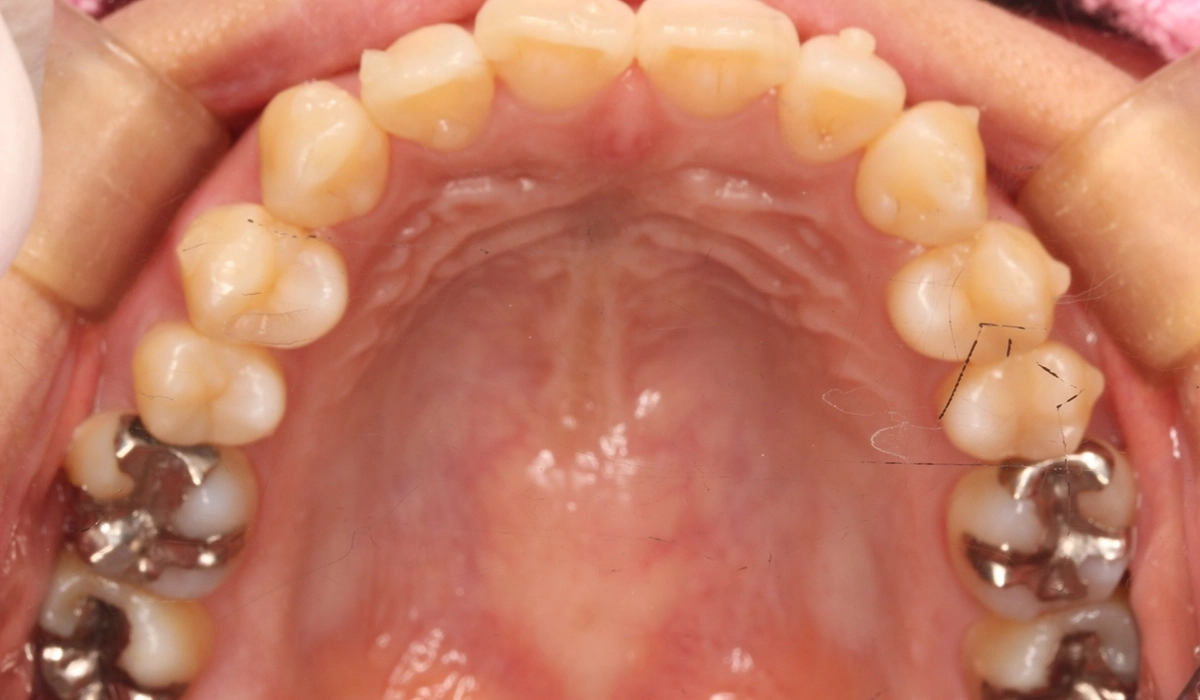

術前:上顎

術後:上顎